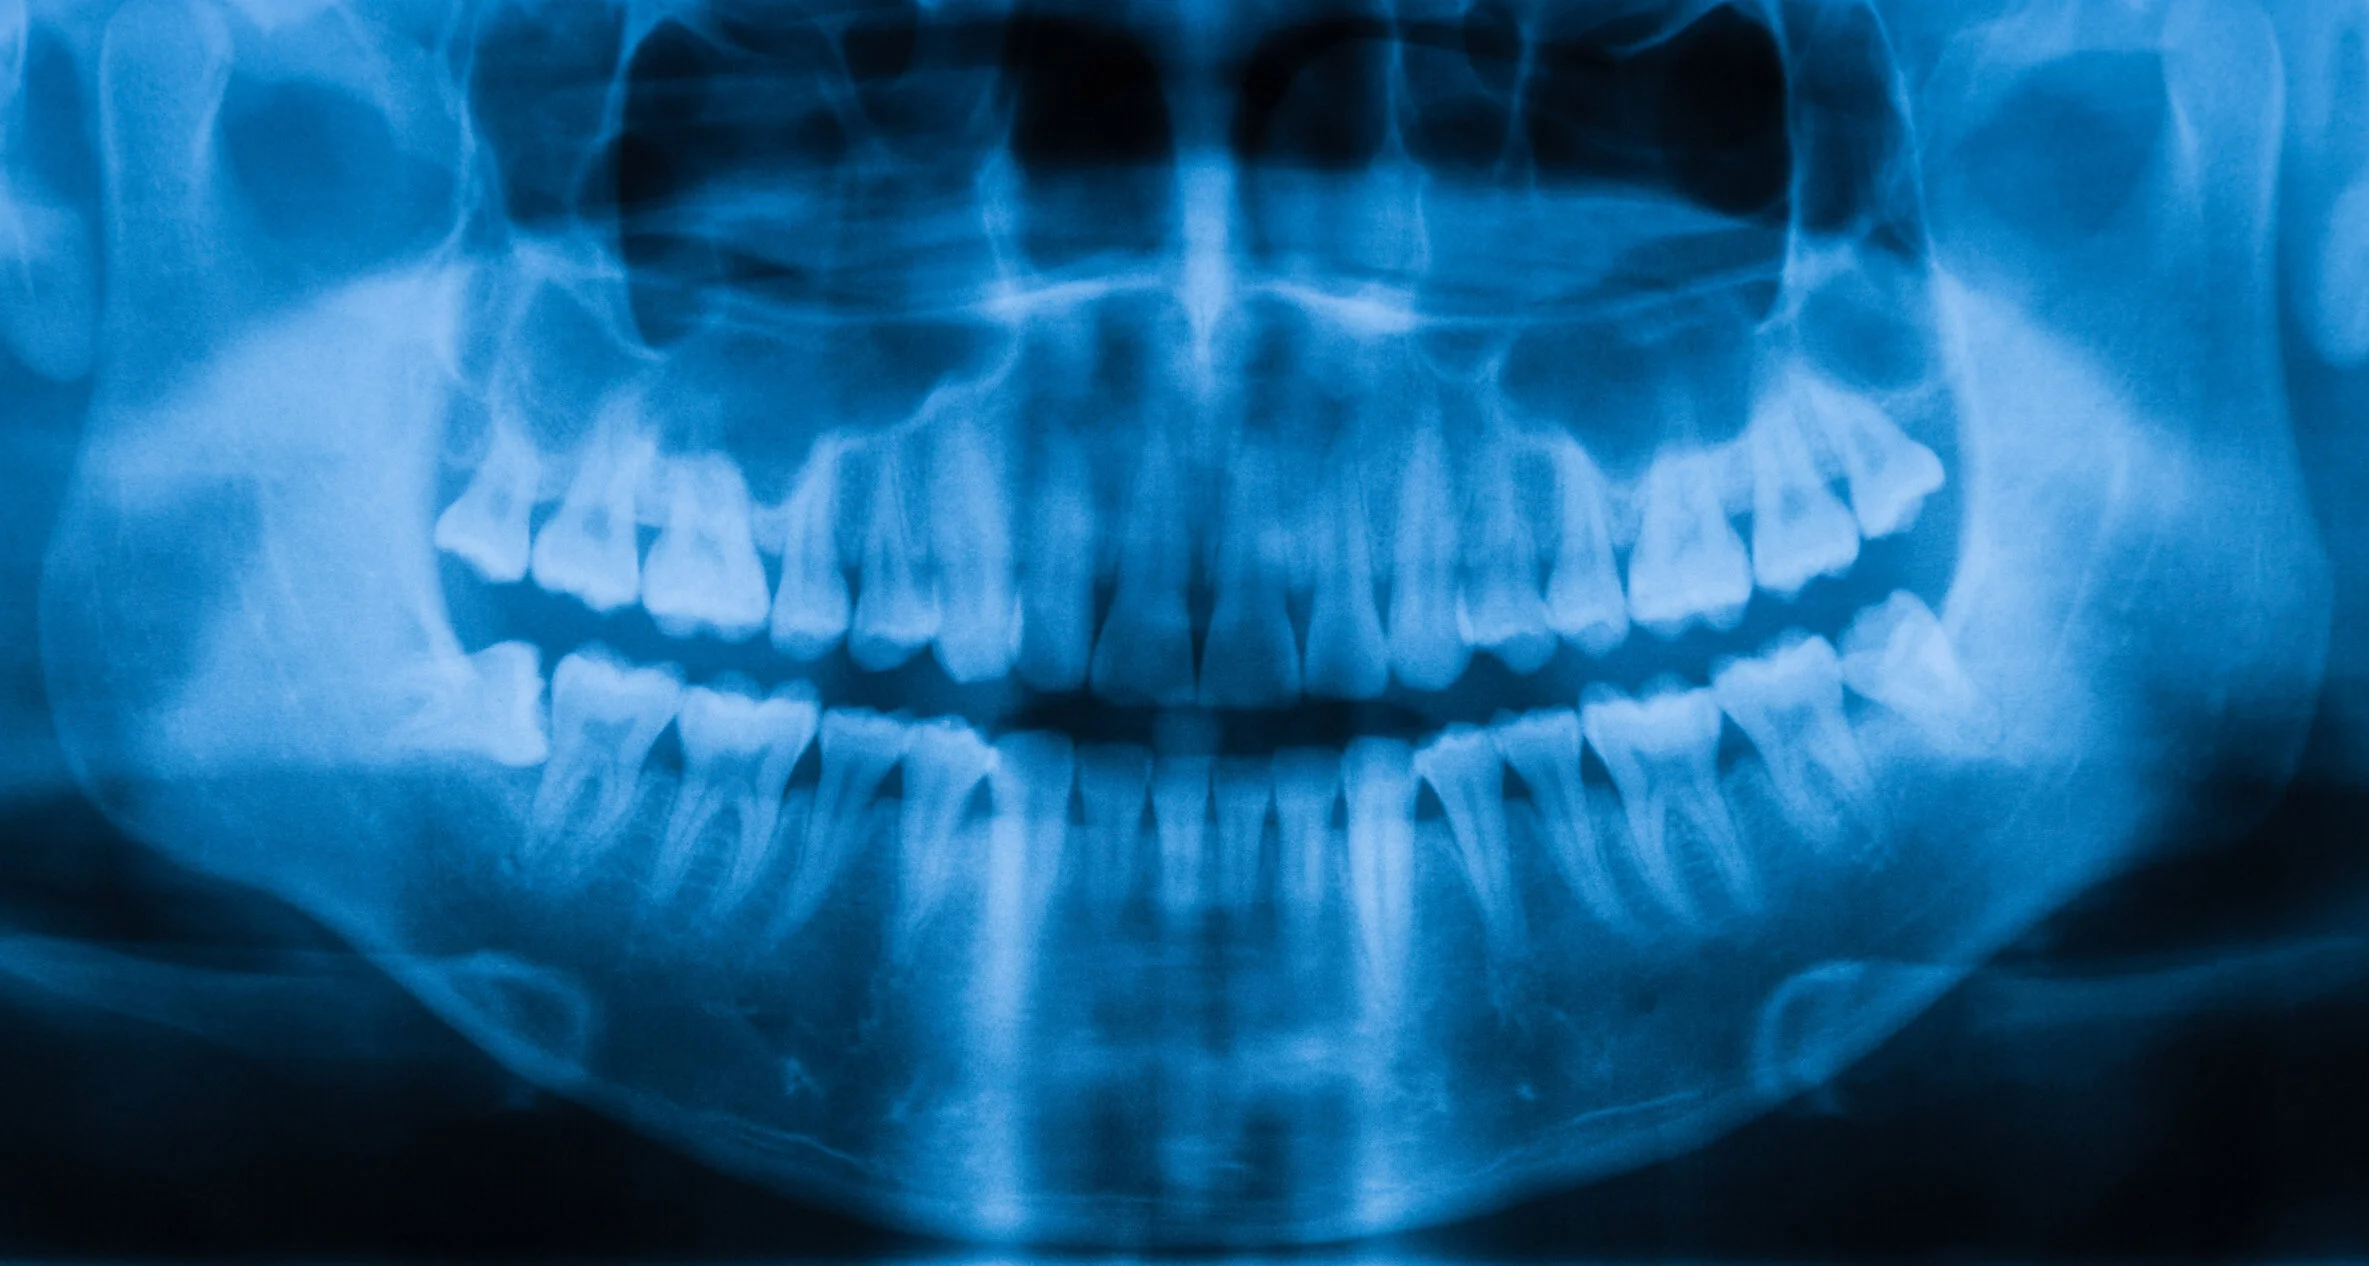

Dental Imaging (OPG)

What is a Dental Imaging (OPG)?

Dental imaging, particularly an Orthopantomogram (OPG), is a radiographic technique used in dentistry to capture a panoramic or wide-angle view of the upper and lower jaws, teeth, and surrounding structures in a single image. It provides a comprehensive and detailed view of the entire oral and maxillofacial region. This type of dental imaging is valuable for diagnosing various dental and oral health conditions, including but not limited to:

- Identifying dental caries (cavities)

- Evaluating the positioning of teeth and their eruption patterns

- Assessing the health of the jawbone

- Diagnosing dental infections or abscesses

- Planning for orthodontic treatment

- Evaluating the placement of dental implants

- Detecting jaw fractures or tumours

- Assessing the condition of the temporomandibular joints (TMJ)